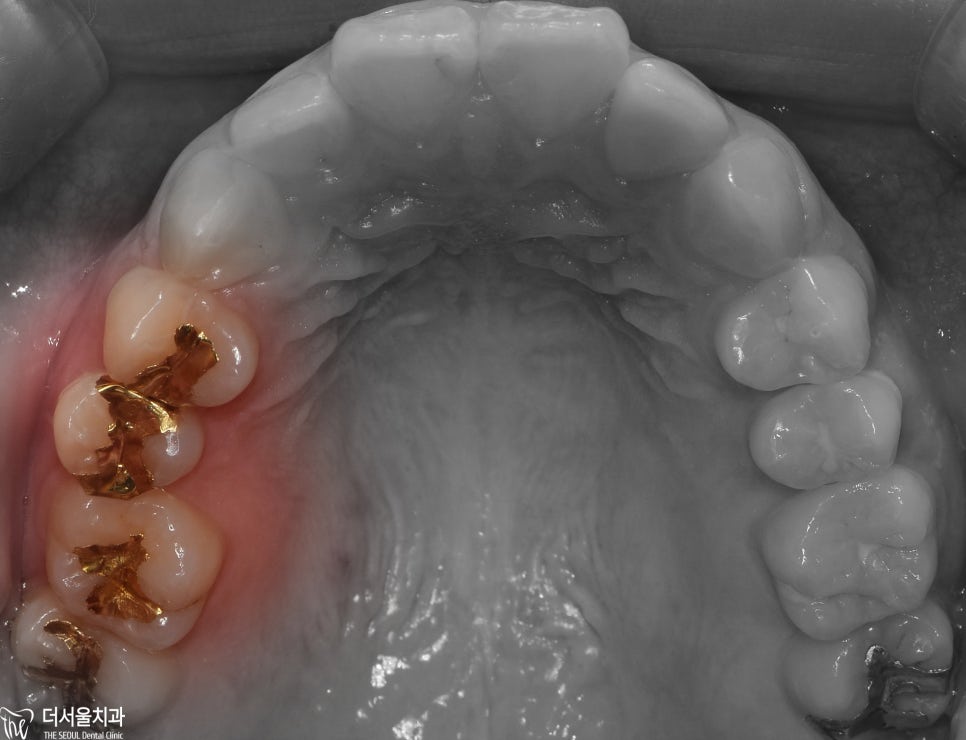

치아의 표면을 보면은,

치아의 색과 비슷한 어태치먼트들이

붙여져 있는 것을 볼 수 있죠?

과거 철사 및 브라켓의 요소를 그냥 함축시켜

놓은 것으로 보면 되겠습니다.